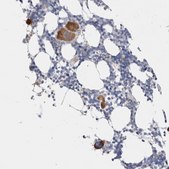

All Prestige Antibodies Powered by Atlas Antibodies are developed and validated by the Human Protein Atlas (HPA) project and as a result, are supported by the most extensive characterization in the industry.

The Human Protein Atlas project can be subdivided into three efforts: Human Tissue Atlas, Cancer Atlas, and Human Cell Atlas. The antibodies that have been generated in support of the Tissue and Cancer Atlas projects have been tested by immunohistochemistry against hundreds of normal and disease tissues and through the recent efforts of the Human Cell Atlas project, many have been characterized by immunofluorescence to map the human proteome not only at the tissue level but now at the subcellular level. These images and the collection of this vast data set can be viewed on the Human Protein Atlas (HPA) site by clicking on the Image Gallery link. We also provide Prestige Antibodies® protocols and other useful information.

• IHC tissue array of 44 normal human tissues and 20 of the most common cancer type tissues.